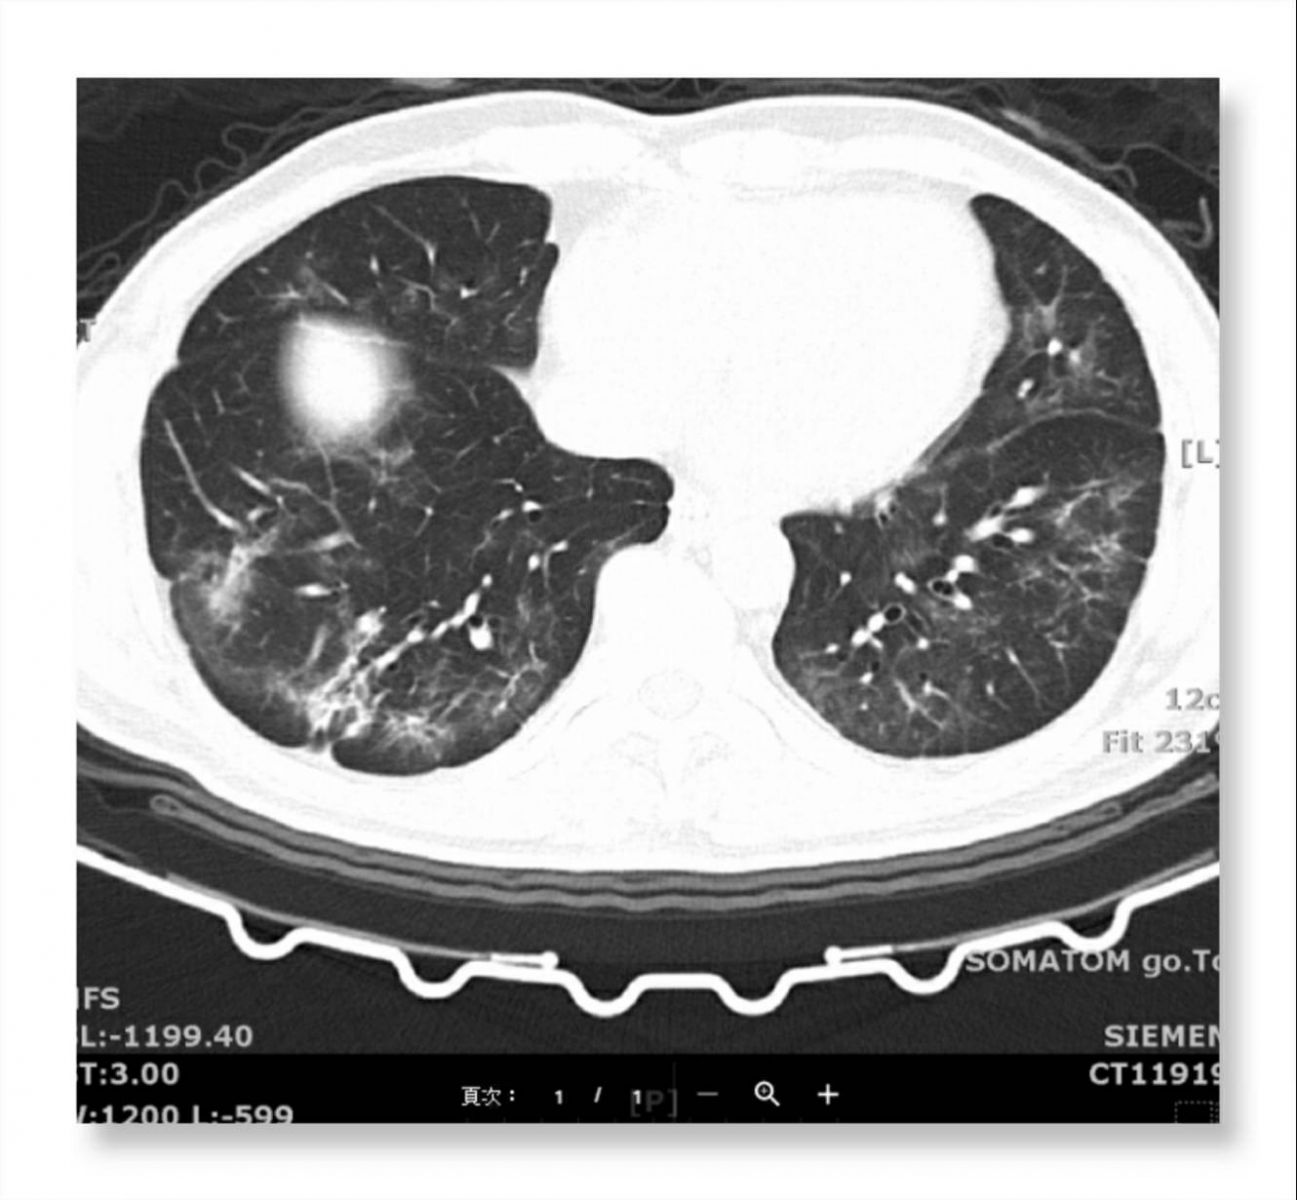

一位新冠肺炎患者經過了三周多的治療,在三次檢測轉陰後,電腦斷層仍顯示右下肺葉(圖的左邊下方)出現纖維化,兩側肺葉出現毛玻璃狀浸潤。(圖片提供/振興醫院內科部陶啟偉主任)